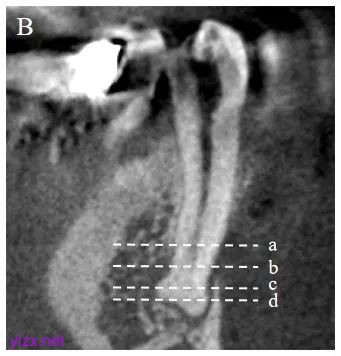

小视野锥束计算机断层扫描(CBCT)示根尖明显膨隆,提示存在变异解剖;根尖区大面积低密度影,提示患牙工作长度为26 mm左右;根管冠方2/3为单一根管通路,在根方1/3处(距离牙合面约20 mm)分为颊侧和舌侧根管通路,后续颊侧根管通路在根尖区再次分为近中和远中通路,提示患牙存在三个解剖学根尖孔(图1B)。

图1B 患者治疗前影像学检查结果(2024-09):CBCT可见根尖区膨隆,提示根尖区存在复杂解剖结构,a-d为CBCT的4个水平面截图,其中a平面为单一根管通路图像,b平面可见颊侧与舌侧各管通路分离影像(箭头),c平面可见颊侧根管通路再次分为近中和远中通路,根尖区存在3个解剖学根尖孔(箭头),d平面可见根尖区大面积低密度影及颊侧根表面膨隆影像